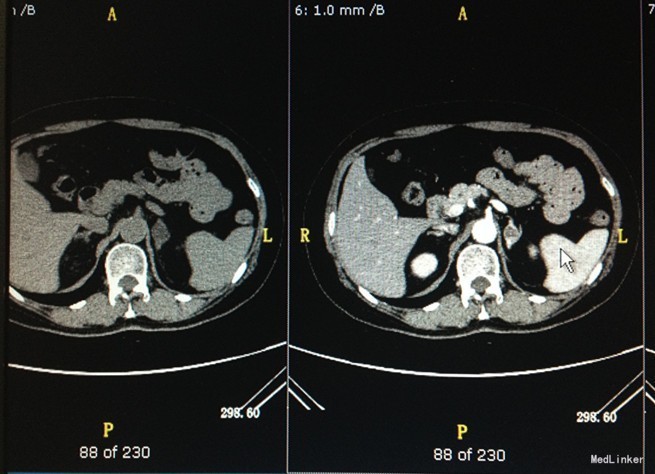

入院查体:无明显异常。 辅助检查: 肾上腺皮质激素系列 8:00 15:00 24:00 促肾上腺皮质激素测定ACTH 9.36pg/ml 7.9pg/ml 4.67pg/ml 皮质醇测定COR 545.9nmol/L 227.5nmol/L 137.7nmol/L 卧位 立位 血管紧张素II测定 41.00ng/mL 71.00ng/mL 血管紧张素I测定 0.53ng/mL 3.6ng/mL 醛固酮测定ALD 0.1ng/mL 0.14ng/mL 卧位 立位 血管紧张素II测定 29.00ng/mL 57.00ng/mL 血管紧张素I测定 0.27ng/mL 0.98ng/mL 醛固酮测定ALD 0.15ng/mL 0.18ng/mL 肝胆脾胰彩超:肝胆脾胰双肾膀胱未见明显异常,残尿量约:17ml。肾上腺增强:左侧肾上腺腺瘤可能性大,请结合临床。双肾小囊肿。

诊断:左肾上腺占位性病变 高血压 治疗:关于肾上腺占位,患者不愿行手术治疗,继续非洛地平降压。